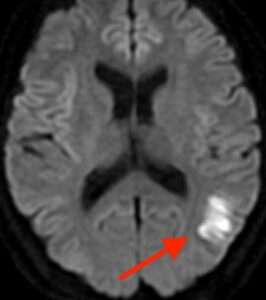

たとえば、脳の血管がつまる脳梗塞は、発症してすぐにはCTで写りません。MRIでも「拡散強調画像」という検査法を撮らなければ写らない時期があります。脳梗塞を疑い、MRIで拡散強調画像を撮って初めて、発症したばかりの脳梗塞を発見することができます。

ASL(arterial spin labeling)法とは、脳の血流状態を評価する方法で、図のように描かれます。1) 2)